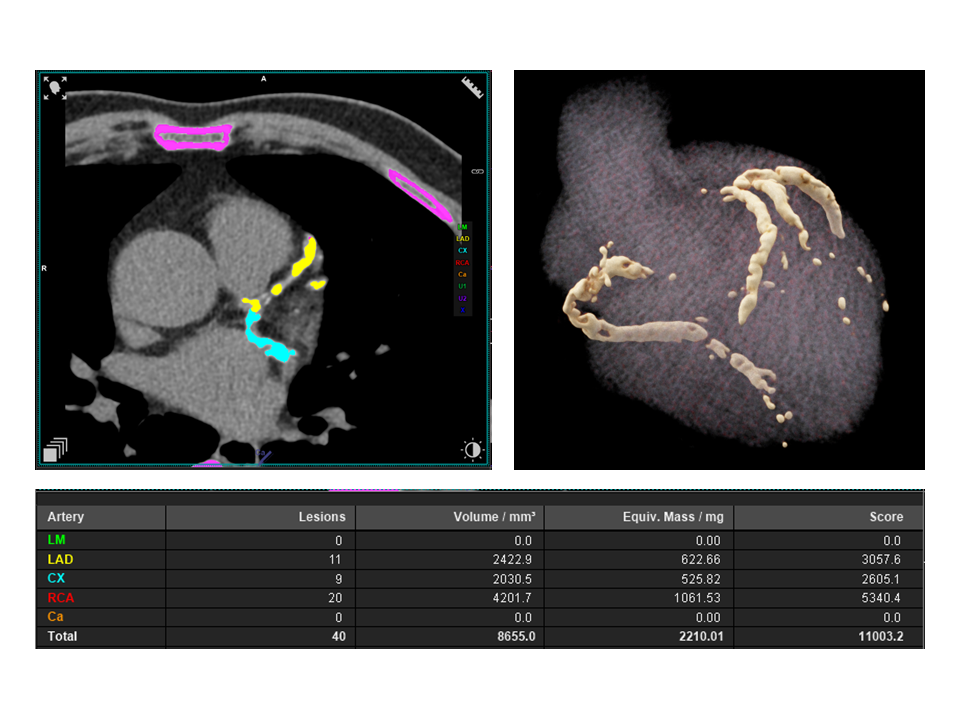

A 62-year-old male with poorly controlled type II and Hypercholesterolemia, an active lifestyle, no cardiac or chest symptoms, underwent an annual health checkup, and low-dose CT lung screening showed extensive coronary artery calcification. The patient was subsequently referred for CCTA to further evaluate coronary artery disease risk. Non-contrast calcium scoring revealed an Agatston score of 11,000, indicating an extremely high calcific burden.

To overcome the diagnostic limitations typically associated with such extensive calcification, the patient was scanned using the Quantum Plus HD protocol on the NAEOTOM Alpha system. The ultra high-resolution PCD-CT acquisition with spectral data reconstruction6 enabled clear visualization of the coronary lumen and confident assessment of stenosis, despite the dense calcific burden. Invasive catheter angiography was avoided in this case.